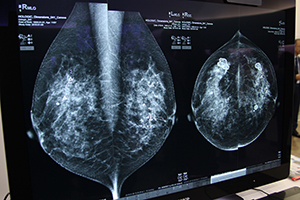

ホロジックジャパンは,検診からバイオプシーまでの一貫したブレストケアをテーマに,マンモグラフィやバイオプシーシステム,診断支援ソフトウエアなどを展示した。今回,展示の核となったのが,日本国内初展示となった新製品の腹臥位式乳腺バイオプシー専用システム「Affirm Prone Biopsy System」である。FPD搭載やトモシンセシス撮影が特徴の装置で,デジタル式乳房X線撮影装置「Selenia Dimensions」と同等の機能が実装されている。Selenia Dimensionsによるトモシンセシスガイド下バイオプシーの有用性が認識されている米国では,腹臥位式システムへの搭載ニーズが高く,これに応えるシステムとして開発された。このほか,Selenia Dimensions専用のバイオプシーガイドシステム「Affirm」の新しいオプション機能や,乳腺画像診断を支援する各種ソフトウエアなどを紹介した。

デジタル式乳房X線撮影装置Selenia Dimensionsは,乳腺の重なりで埋もれてしまう病変を検出しやくするトモシンセシス撮影が特徴のマンモグラフィシステムである。米国内では1000万人以上の女性が受診し,大規模スタディに用いられ,多くの臨床論文が発表されているなど,豊富な実績を有する。今回は,ユーザーのニーズに合わせてカスタマイズが可能なユニバーサルコンソールとともに展示した。